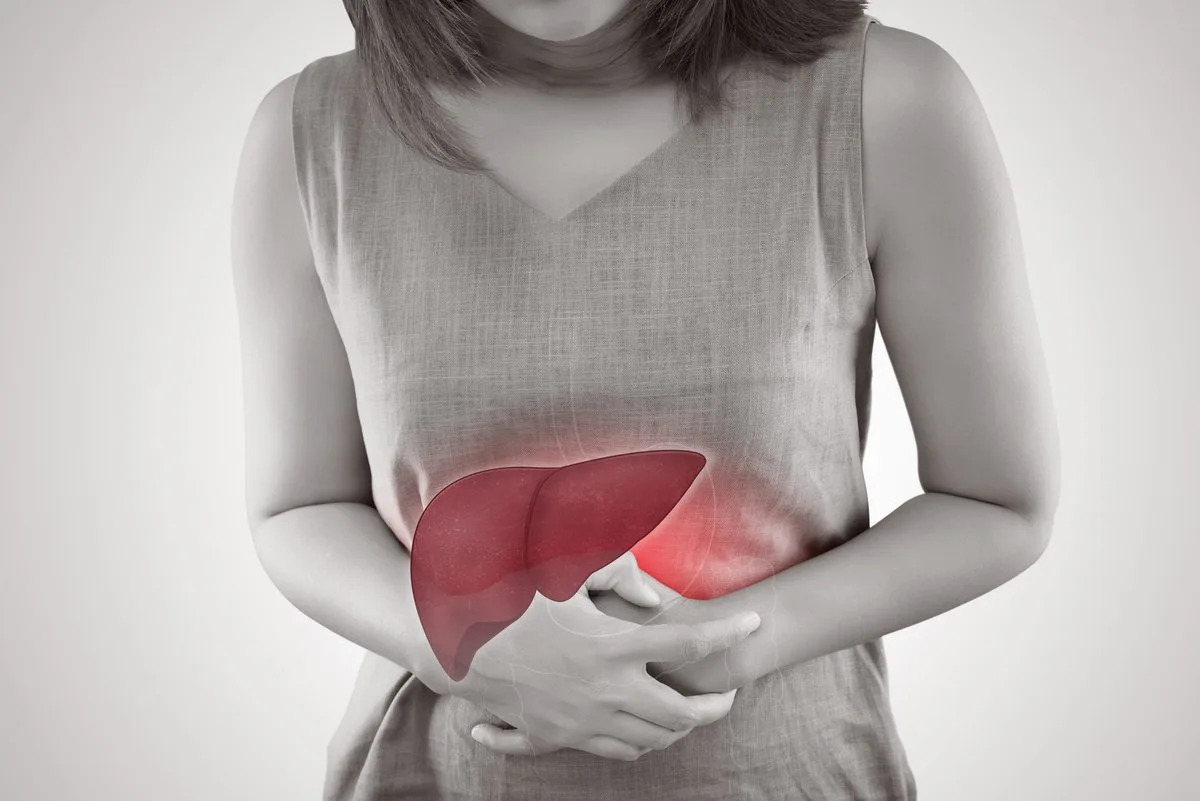

آیا می دانستید کبد که در قسمت راست بدن و بالای شکم قرار دارد، بزرگترین اندام داخلی بدن نیز به شمار می آید؟ و در صورت رعایت نکردن برخی مسائل، مشکلاتی به همان اندازه بزرگ، برای شما به وجود می آورد؟ کبد چرب یکی از شایع ترین مشکلات این عضو بدن است. بنابراین آگاهی از اینکه علائم کبد چرب چیست و چگونه درمان می شود، لازم و ضروری به نظر می رسد.

کبد چرب می تواند کبد را بزرگ کند و زمانی هم که این اتفاق شکل می گیرد، ممکن است فرد مبتلا، درد یا ناراحتی در قسمت سمت راست بالای شکم «بین باسن و قفسه سینه» احساس کند. در برخی موارد علائم اولیه این بیماری می تواند شامل موارد زیر شود:

قبل از به جریان افتادن خون از دستگاه گوارش، این کبد است که خون تقویت شده را به همه قسمت های بدن ارسال کرده و به عنوان فیلتر بدن عمل می کند، اما این فیلتر زمانی به مشکل می خورد که چربی آن به بیش از حد مجاز برسد و به اصطلاح کبد، چرب شود. اگر به دنبال علت چرب شدن کبد به همراه راه های درمان آن هستید و می خواهید اطلاعات خود را در زمینه کبد افزایش دهید، با ما در این مقاله همراه باشید.

بنا به نظر برخی پزشکان بیماری کبد چرب را بیماری خاموش هم می نامند و دلیلش این است که فرد در صورت دچار شدن به مشکلات کبدی هیچ علامت یا علائمی را تجربه نمی کند، حتی اگر بیماری پیشرفت داشته باشد. با وجود این تفاسیر بیماری کبد چرب می تواند کبد را بزرگ کند و زمانی هم که این اتفاق شکل می گیرد، ممکن است فرد مبتلا، درد یا ناراحتی در قسمت سمت راست بالای شکم «بین باسن و قفسه سینه» احساس کند.